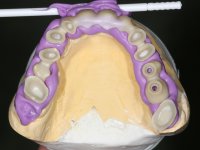

Alginate impressions were made at both arches arcades, accompanied by intermaxillary registration relations and collecting information with facial bow facial bow. In the laboratory, a provisional bridge with 13 elements in autopolymerizable acrylic was built, in which a metallic reinforcement was included. Teeth 1.7 / 1.4 / 1.3 / 2.2 / 2.3 / 2.4 and 2.6 were used as pillars. The metal-ceramic bridge was removed after performing longitudinal cuts with diamond burs. The dental abutments were reprepared and the temporary bridge was relined in the mouth with self-curing acrylic. After confection of the provisional bridge, a gingival epithesis was made using composite resin with gingival tonality in order to function as a mock-up, which allowed the patient to preview the possibility of using gingiva shade ceramics in the final work. This option was approved by the patient. Subsequently, the placement of two implants in the first quadrant was planned and executed. The provisional monoblock was removed for placement of the implants, and after surgery was again cemented provisionally. After the osseointegration period, the impressions were made to the maxilla. In the anterior zone, impregnated gingival retraction cords were used, and in the posterior areas, kaolin paste was used. Implant printing utilized the open tray technique. The printing material used was soft and regular putty addition silicone, both fast-setting. In the laboratory, the model of provisional restorations and the gingiva epithesis mock-up served as orientation for waxing the infrastructure. The plaster work model and the waxing of the infrastructure were placed in a laboratory scanner and yielded a digital work model, in which the scanning of the waxed infrastructure was superimposed. This overlay facilitated the CAD design of the Zr infrastructure. Subsequently, the CAD drawing for a CAM milling process provided the Zr pieces. The infrastructure was pigmented with a pinkish coloration, which favors the subsequent placement of gum shade ceramic. During the modeling of the infrastructure, the need to increase the occlusal wear on tooth 1.4 was detected. This was done in the real working model cast and an acrylic wear control guide was created, which accompanied the proof of the infrastructures. Corrective wear and Zr parts test were performed in mouth. During the test, the color choice of the gum shade ceramic was reassessed. The treatment was finished in the laboratory, and after approval by the patient, was definitively placed in the mouth.